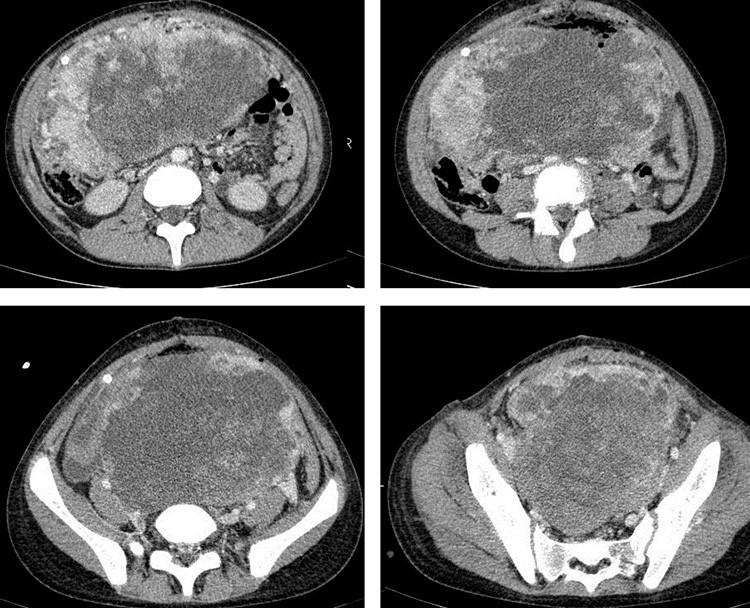

• КТ (расшифровка: компьютерная томография), МРТ (расшифровка: магнитно-резонансная томография), ПЭТ-КТ (расшифровка: позитронно-эмиссионная томография, совмещенная с КТ). Эти обследования необходимы, чтобы рассмотреть структуры организма послойно и визуализировать опухоль. Они показывают, как сильно распространен патологический опухолевый процесс на находящиеся рядом ткани и органы, есть ли поражение костей. КТ – это самый чувствительный метод для обнаружения метастазов в легких. Проведение МРТ и КТ головного мозга необходимо, чтобы обнаружить и визуализировать герминогенные новообразования эпифиза.

• Risunok8.jpgРисунок 8. КТ органов брюшной полости – на снимках вы можете увидеть опухоль яичника.